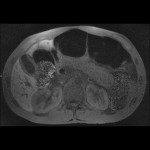

- T1 Pre